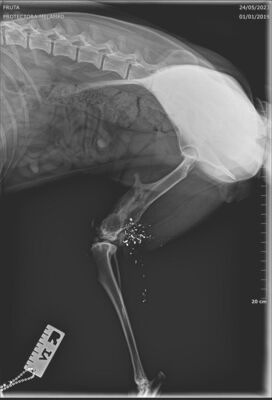

Fruta wurde kastriert und ihr alte Verletzung wurde dabei auch gleich geröngt. Dabei kam heraus, dass Fruta eine Schussverletzung hat und immer noch Schrot im Bein hat. Die Röntgenbilder sind weiter unten zu finden.

Fruta’s Hinterbein wurde beim Spezialisten abgeklärt. Das Bein ist steif, sie hat aber keine Schmerzen. Es stört sie auch nicht, sie läuft, rennt und hüpft auch ohne Probleme aufs Sofa.